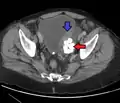

- Los divertículos uretrales se encuentran generalmente en mujeres de 30 a 70 años, entre el 1 y el 6% de las mujeres adultas. Dado que la mayoría de los casos no presentan síntomas, se desconoce la verdadera incidencia. Los síntomas pueden variar desde infecciones frecuentes del tracto urinario, relaciones sexuales dolorosas (dispareunia) o síntomas debidos al cáncer. Un divertículo uretral se encuentra en la pared vaginal anterior, 1 a 3 cm dentro del introito vaginal. Se prefiere la resonancia magnética como método de imagen de elección debido a su excelente resolución de tejidos blandos. En las imágenes ponderadas en T2, muestra una señal alta en el divertículo debido a la presencia de líquido en su interior. La ecografía vaginal es muy sensible para diagnosticar el divertículo, pero depende en gran medida de las habilidades del operador.[17]